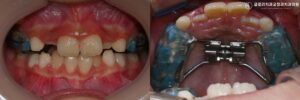

어린이 덧니교정, 상악골 확장 으로 시작하는 1차 교정치료 계획 (ft. 하악 확장장치도 있나요?)

겨울방학이 시작되면서 교정 상담을 받으러오는 어린이 환자가 부쩍 늘어나는 시기입니다. 24.01.18 아이가 활짝 웃을 때 아직 치아가 제대로 나오지 않았거나 삐뚤빼뚤한 앞니가 보인다면 부모님 마음이 편치 않습니다. 또한 지금 교정을…